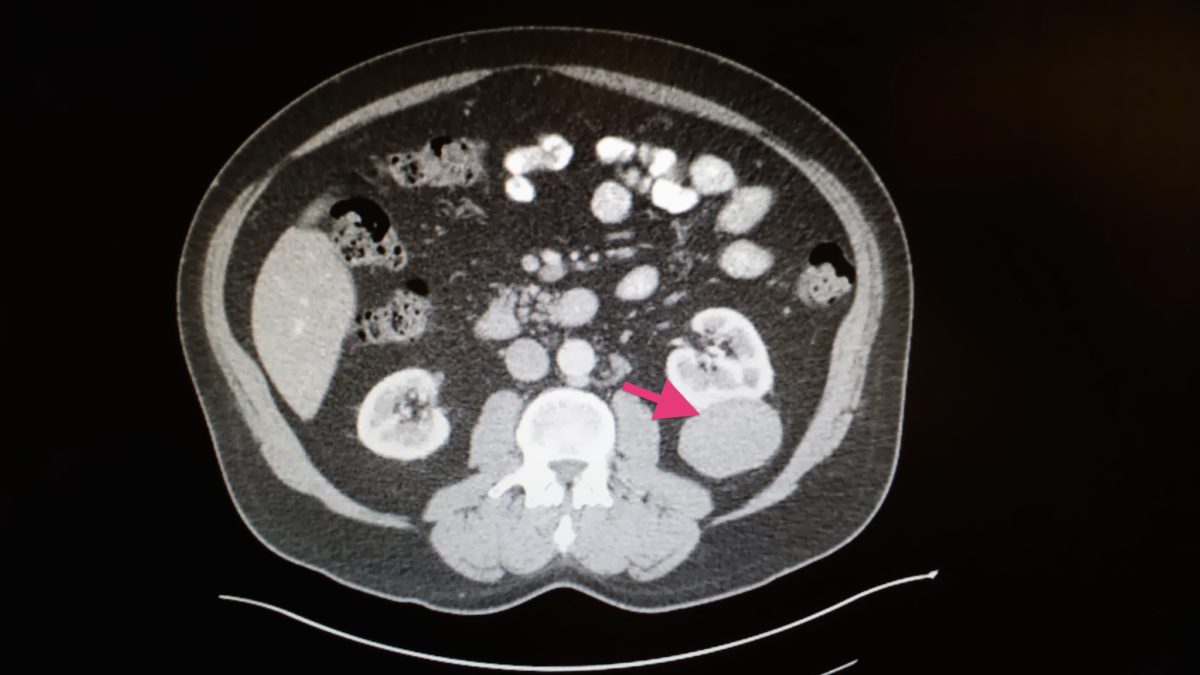

If the renal carcinoma hasn’t spread and is just in the kidney than you have great potential for a positive outcome no matter how large it is. There, specialists in urology, oncology, neurosurgery and other areas collaborated on a multidisciplinary approach that helped craig regain his health. After waking up one night to searing abdominal pain and night sweats, he received an ultrasound and ct scan that revealed a large mass on his kidney that spread to his lungs.